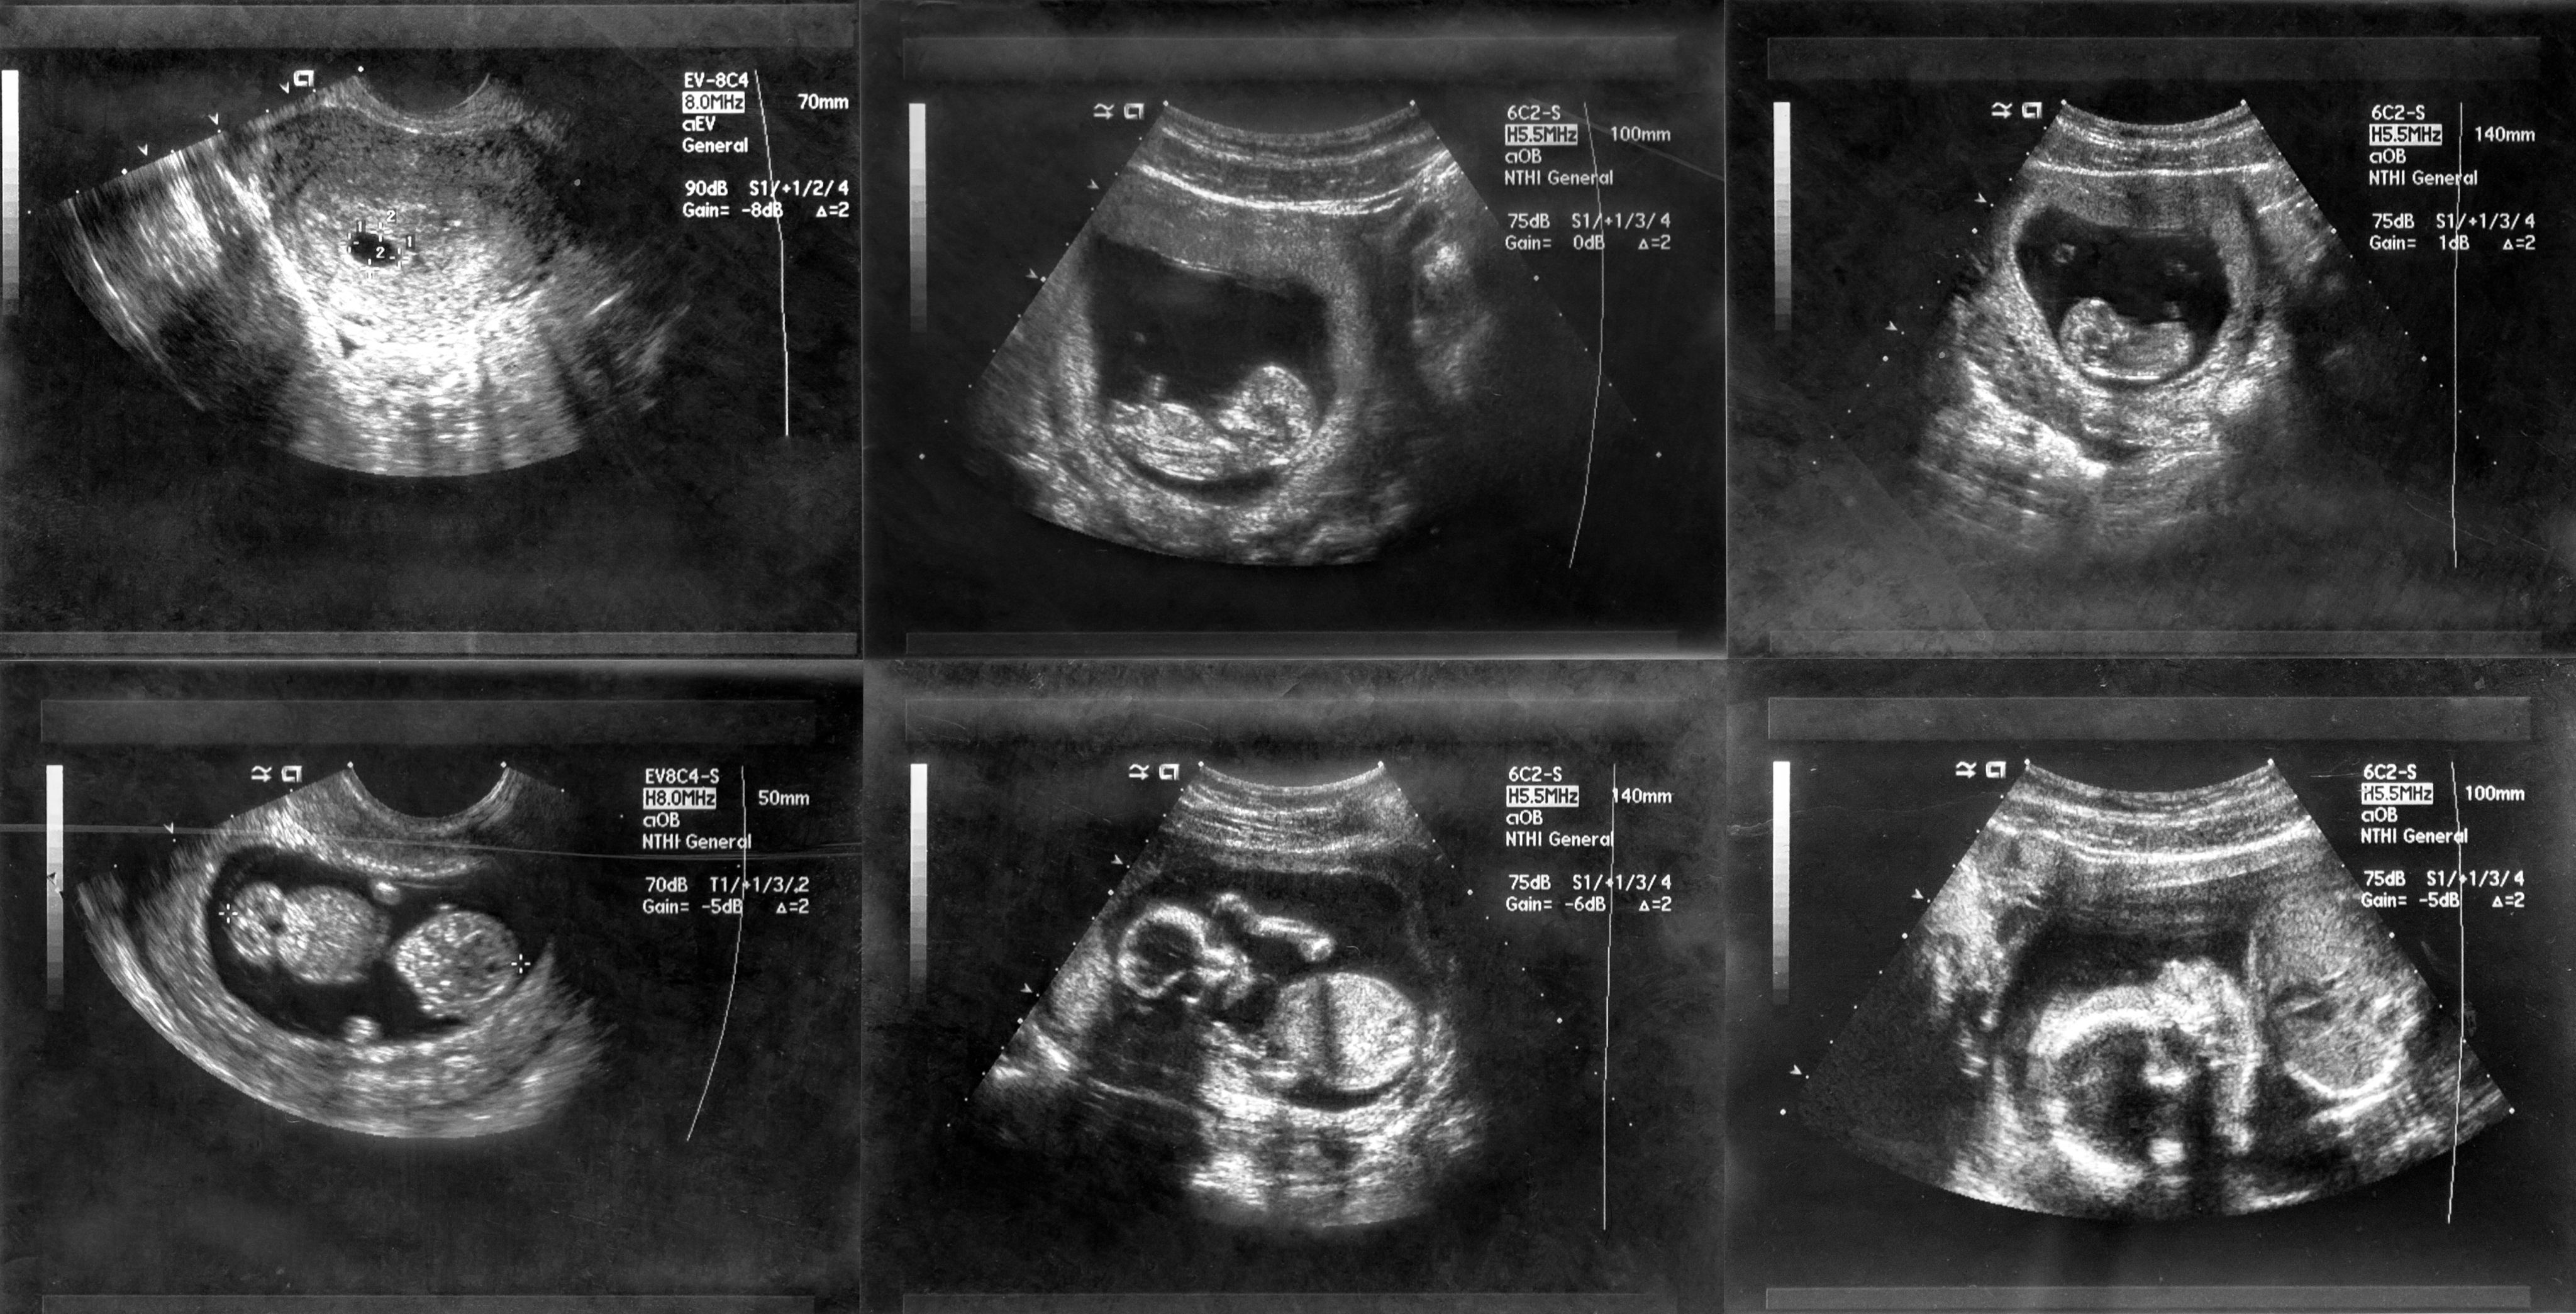

An international authority on the use of ultrasound in gynaecological disorders as well as the management of early pregnancy complications, Professor Tom Bourne’s research has been pivotal in setting the standard for the early diagnosis of miscarriage.

“For me the issue came to a head when I was chairing an early pregnancy session at the International Society for Ultrasound in Obstetrics and Gynaecology meeting in Prague in 2010. I asked the audience what they used as a cut-off value for mean gestation sac diameter to define miscarriage, and the answers ranged from a very worrying 2 to a more reassuring 20 mm.”

An accurate diagnosis in the first trimester (the first 12 weeks of pregnancy) is vital since a misdiagnosis could result in a healthy pregnancy being inadvertently terminated. However, for Professor Bourne, Chair in Gynaecology in the Department of Metabolism, DIgestion and Reproduction, it seemed that the then-existing criteria used to define miscarriage was “less than watertight”.

Between 2011 and 2015, the Imperial team led by Professor Bourne collected ultrasound data from over 3,000 women in the UK. They found that the risk of misdiagnosis using embryo size measurements and an apparent lack of a visible heartbeat on ultrasonography could be as high as 8% – just over 1 in 12 – potentially resulting in cases of unnecessary termination of a wanted pregnancy.

This prompted a publication in the New England Journal of Medicine that used the Imperial data to propose new safe diagnostic criteria. Their discovery led to a rapid revision of miscarriage guidelines across the world, including in the UK, France, Italy and the US.

Before this important research, it is possible that thousands of wanted pregnancies throughout the world may have had surgical or medical treatment for a miscarriage based on a misdiagnosis. Indeed, an American study suggests that as many as 12% of women may have been given an incorrect diagnosis of miscarriage using the guidance that existed in the US prior to the Imperial study.